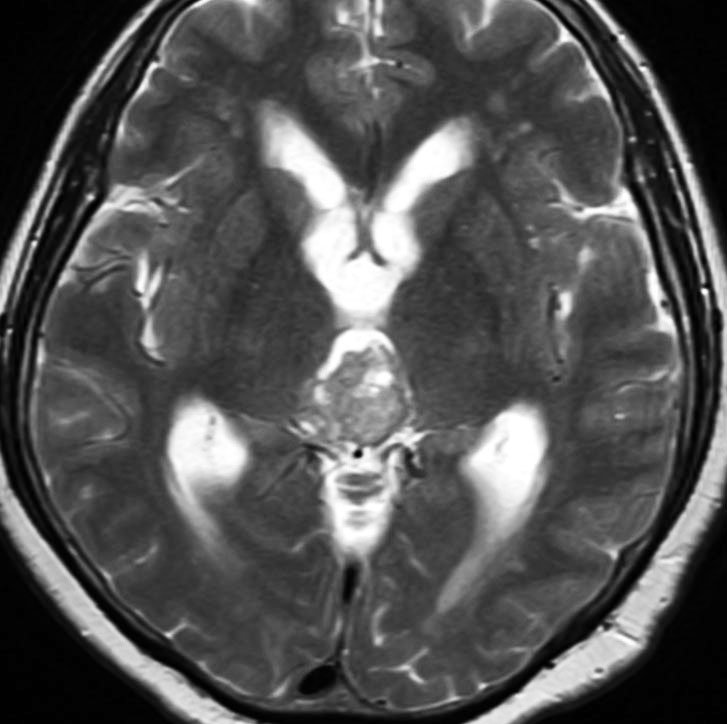

成人女性の松果体細胞腫で充実性腫瘍です。中脳水道が閉塞して軽度の水頭症(頭の中に髄液が溜まる)になってきています。多少凹凸がありますがだいたい楕円形。

もし無症状で見つかったら

松果体腫瘍の手術リスクは高いので,簡単には手術を勧めることができません。でも中脳水道の狭窄がはっきりしていて閉塞の恐れがある時には手術摘出をしたほうがいいでしょう。私も過去に、患者さんに手術を強く勧められないために経過観察して,つらい思いをしたことがあります。中脳水道が急に閉塞すると,急性水頭症となりひどい頭痛から意識障害になって,1日もたないで突然呼吸が停止するということがあります。無症状で何年も経過して,急激な死に至る例があるのです。